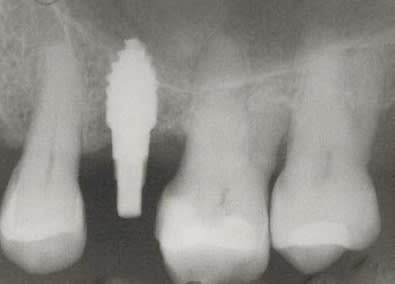

je voulais parler de ce fact pour les implants courts:minimum 4mm os vertical peut suffire (pour eviter un sinus lift externe de tatum) . dans ma pratique depuis quelques années je vois que ca marche , quelques cas cliniques des années passées.

j´ai oublié : 4mm plus 2mm( gagnés par un sinus lift interne)

implant court, mais de grand diamètre ( 5mm et plus ) peut-être un moindre mal.

Pour mes cas, je utilise généralement des 3.5mm et lorsque qu'une stabilité primaire n'est pas atteinte avec un extenseur de 3.0 alors j'utilise du 4.5 mm mais cela est rare.

Le plus important dans un implant sont les 4 premiers millimètres crestales ( c'est pourquoi de nombreuses industries, NB, astra,Bio horizon... ont chosit de faire des implants avec des micro fissures crestales pour augmenter la surface sur ces premiers millimètres et garantir une meilleure stabilité 1aire et 2aire).La partie dans l'os spongieux est moins décisive. Dans un contexte comme celui ci le platform switching est un facteur à ne pas négliger.